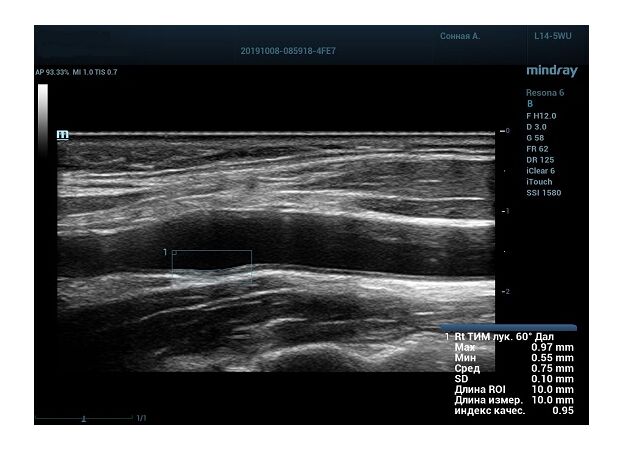

На сегодняшний день измерение IMT происходит автоматическим путем при использовании функции AUTO-IMT. Необходимо указать прибору зону интереса, стандартной длиной (1 см), в которой происходит отслеживание кромок и выдача максимального, среднего и минимального значения.

УЗИ аппараты компании Mindray среднего, экспертного и премиального класса снабжены данной функцией и позволяют контролировать не только полученные значения, но и оценить точность измерения кромки в конкретной зоне по индексу качества. Используя индекс качества, легко решить, можно ли использовать полученное значение.